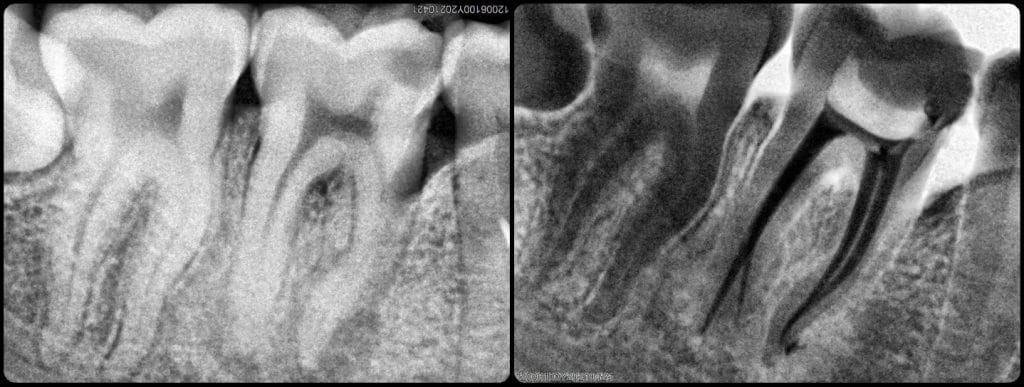

Finding the distal canal split

Mesial cone fit 👌🏻

Obturation. 🖤